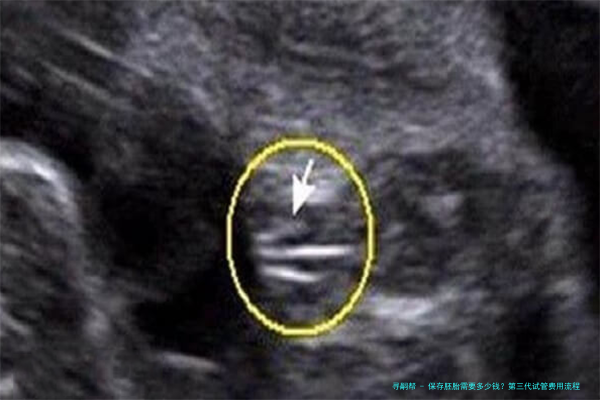

保存胚胎是指将多余的胚胎储存在液氮中,使其处于低温状态,可以长期保持其活力。保存移植技术已广泛应用于临床,为许多不孕夫妇孕育健康婴儿提供了新的机会。在中国大陆保存胚胎的费用因医院和地区而异,通常在3000元至8000元不等。其中较高的金额约为10000-25000元,具体价格取决于医院等因素。

保存母细胞个体的回笼是指将保存在液态氮中的细胞个体取出进行路之人工移植或移植。已获准所使用保存胚芽需要清醒时,需在以上步骤的基础上额外收费。

在中国大海保存母细胞个体复苏的费用因医院和区域而异,一般在五千元至20000元不等。详细价格由不同医院确定。该本钱将考虑多个因素,例如超声检查、促排卵的手术支持、稀释步伐和创造(即ICSI)、培育、裂解团体等,以及控制和治疗的支持项目。为了精确取得信息,请咨询您所在地区的相关诊所或门诊付款结算账目处。